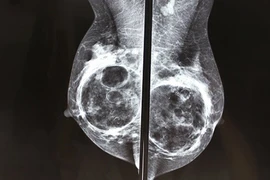

(Kiến Thức) - Nhắc đến phẫu thuật nâng ngực nhiều người nghĩ đến nguy cơ ung thư vú hơn là ung thư máu. Đến cả bác sĩ cũng không nắm rõ về dạng ung thư này.

(Kiến Thức) - Một quý bà với mong muốn có vòng 1 bình thường như những người khác giờ đây mang bộ ngực biến dạng như "càng cua" và còn xấu thậm tệ vì nâng ngực hỏng.